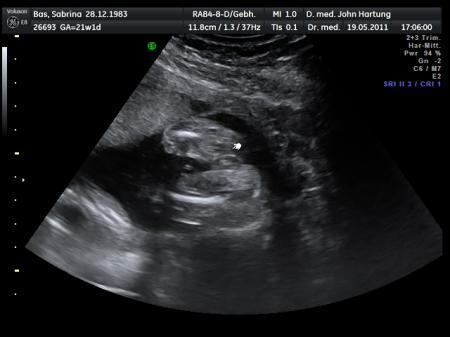

und noch das halbe Hänchen. Der perfekte Beweis das Sie ein Mädchen ist!!!!

Bild zu